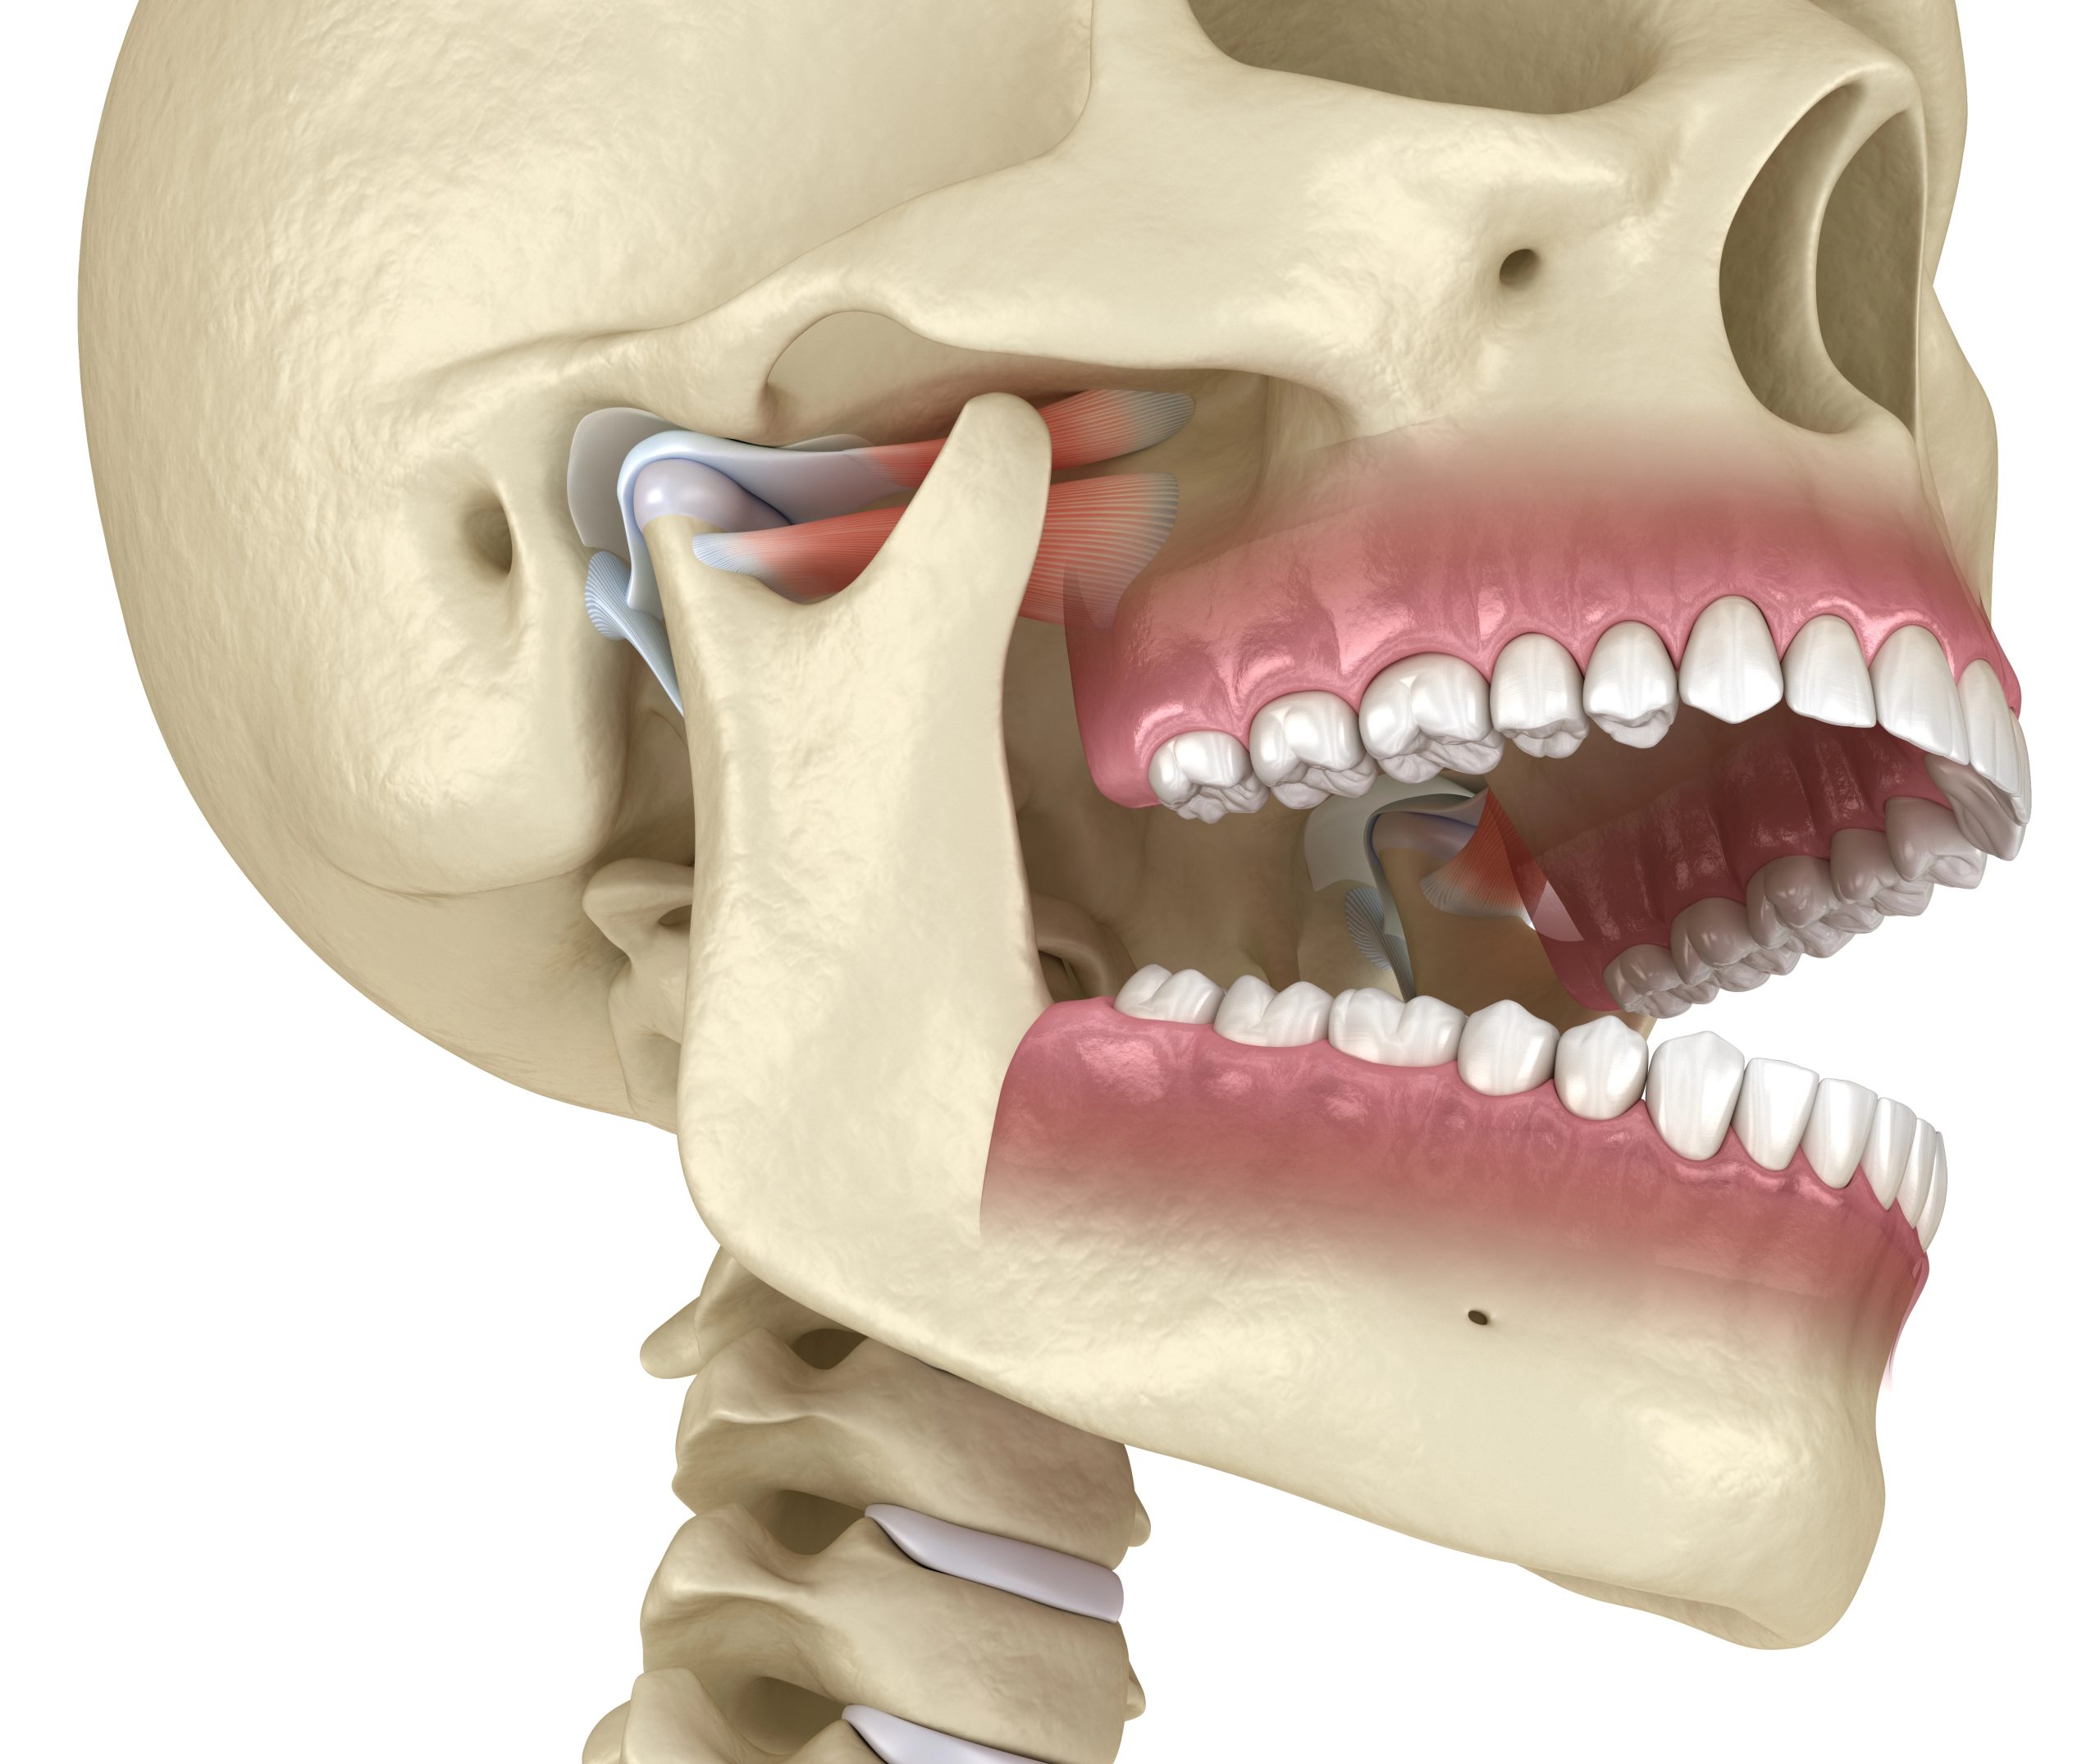

Jaw Discomfort or TMJ Symptoms

PBM may help relax muscles and reduce inflammation associated with jaw discomfort.